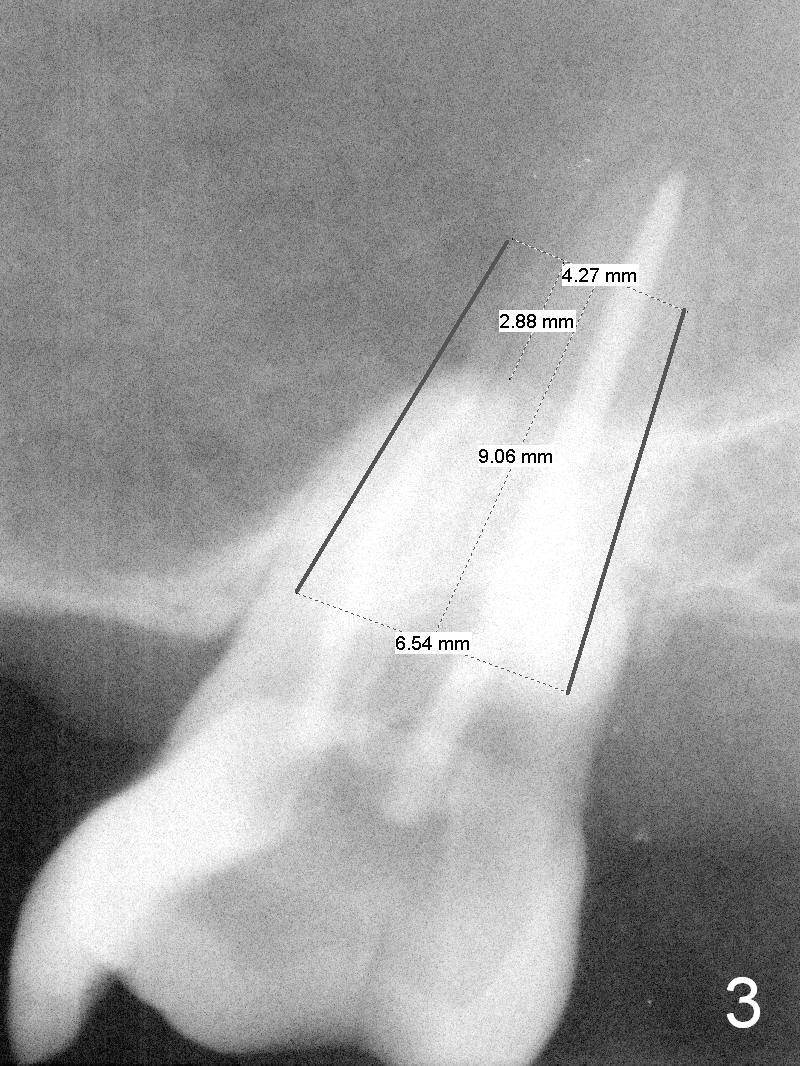

A 60-year-old man requests implant at #15, since the tooth with distal subgingival caries has kept fracturing in the last 4 years (Fig.1,2). Metronidazole will be used for socket disinfection. Since the socket is most likely large and single (fused roots), a large IBS implant (Fig.3,4: 6 or 6.5x9 or 11 mm) is to be placed following initial 7 mm depth of drilling or bone expansion (Fig.4). Prepare bone graft for sinus lift and gap closure. His bone is soft at #10; underprep is necessary at #15. An abutment is expected to be 6x4(3) mm (Fig.4). Since he is partially edentulous, an immediate provisional should be large enough to close the socket, but small enough not to be interfered with the partial denture on and off. Take photos of #10 to show no metal show.